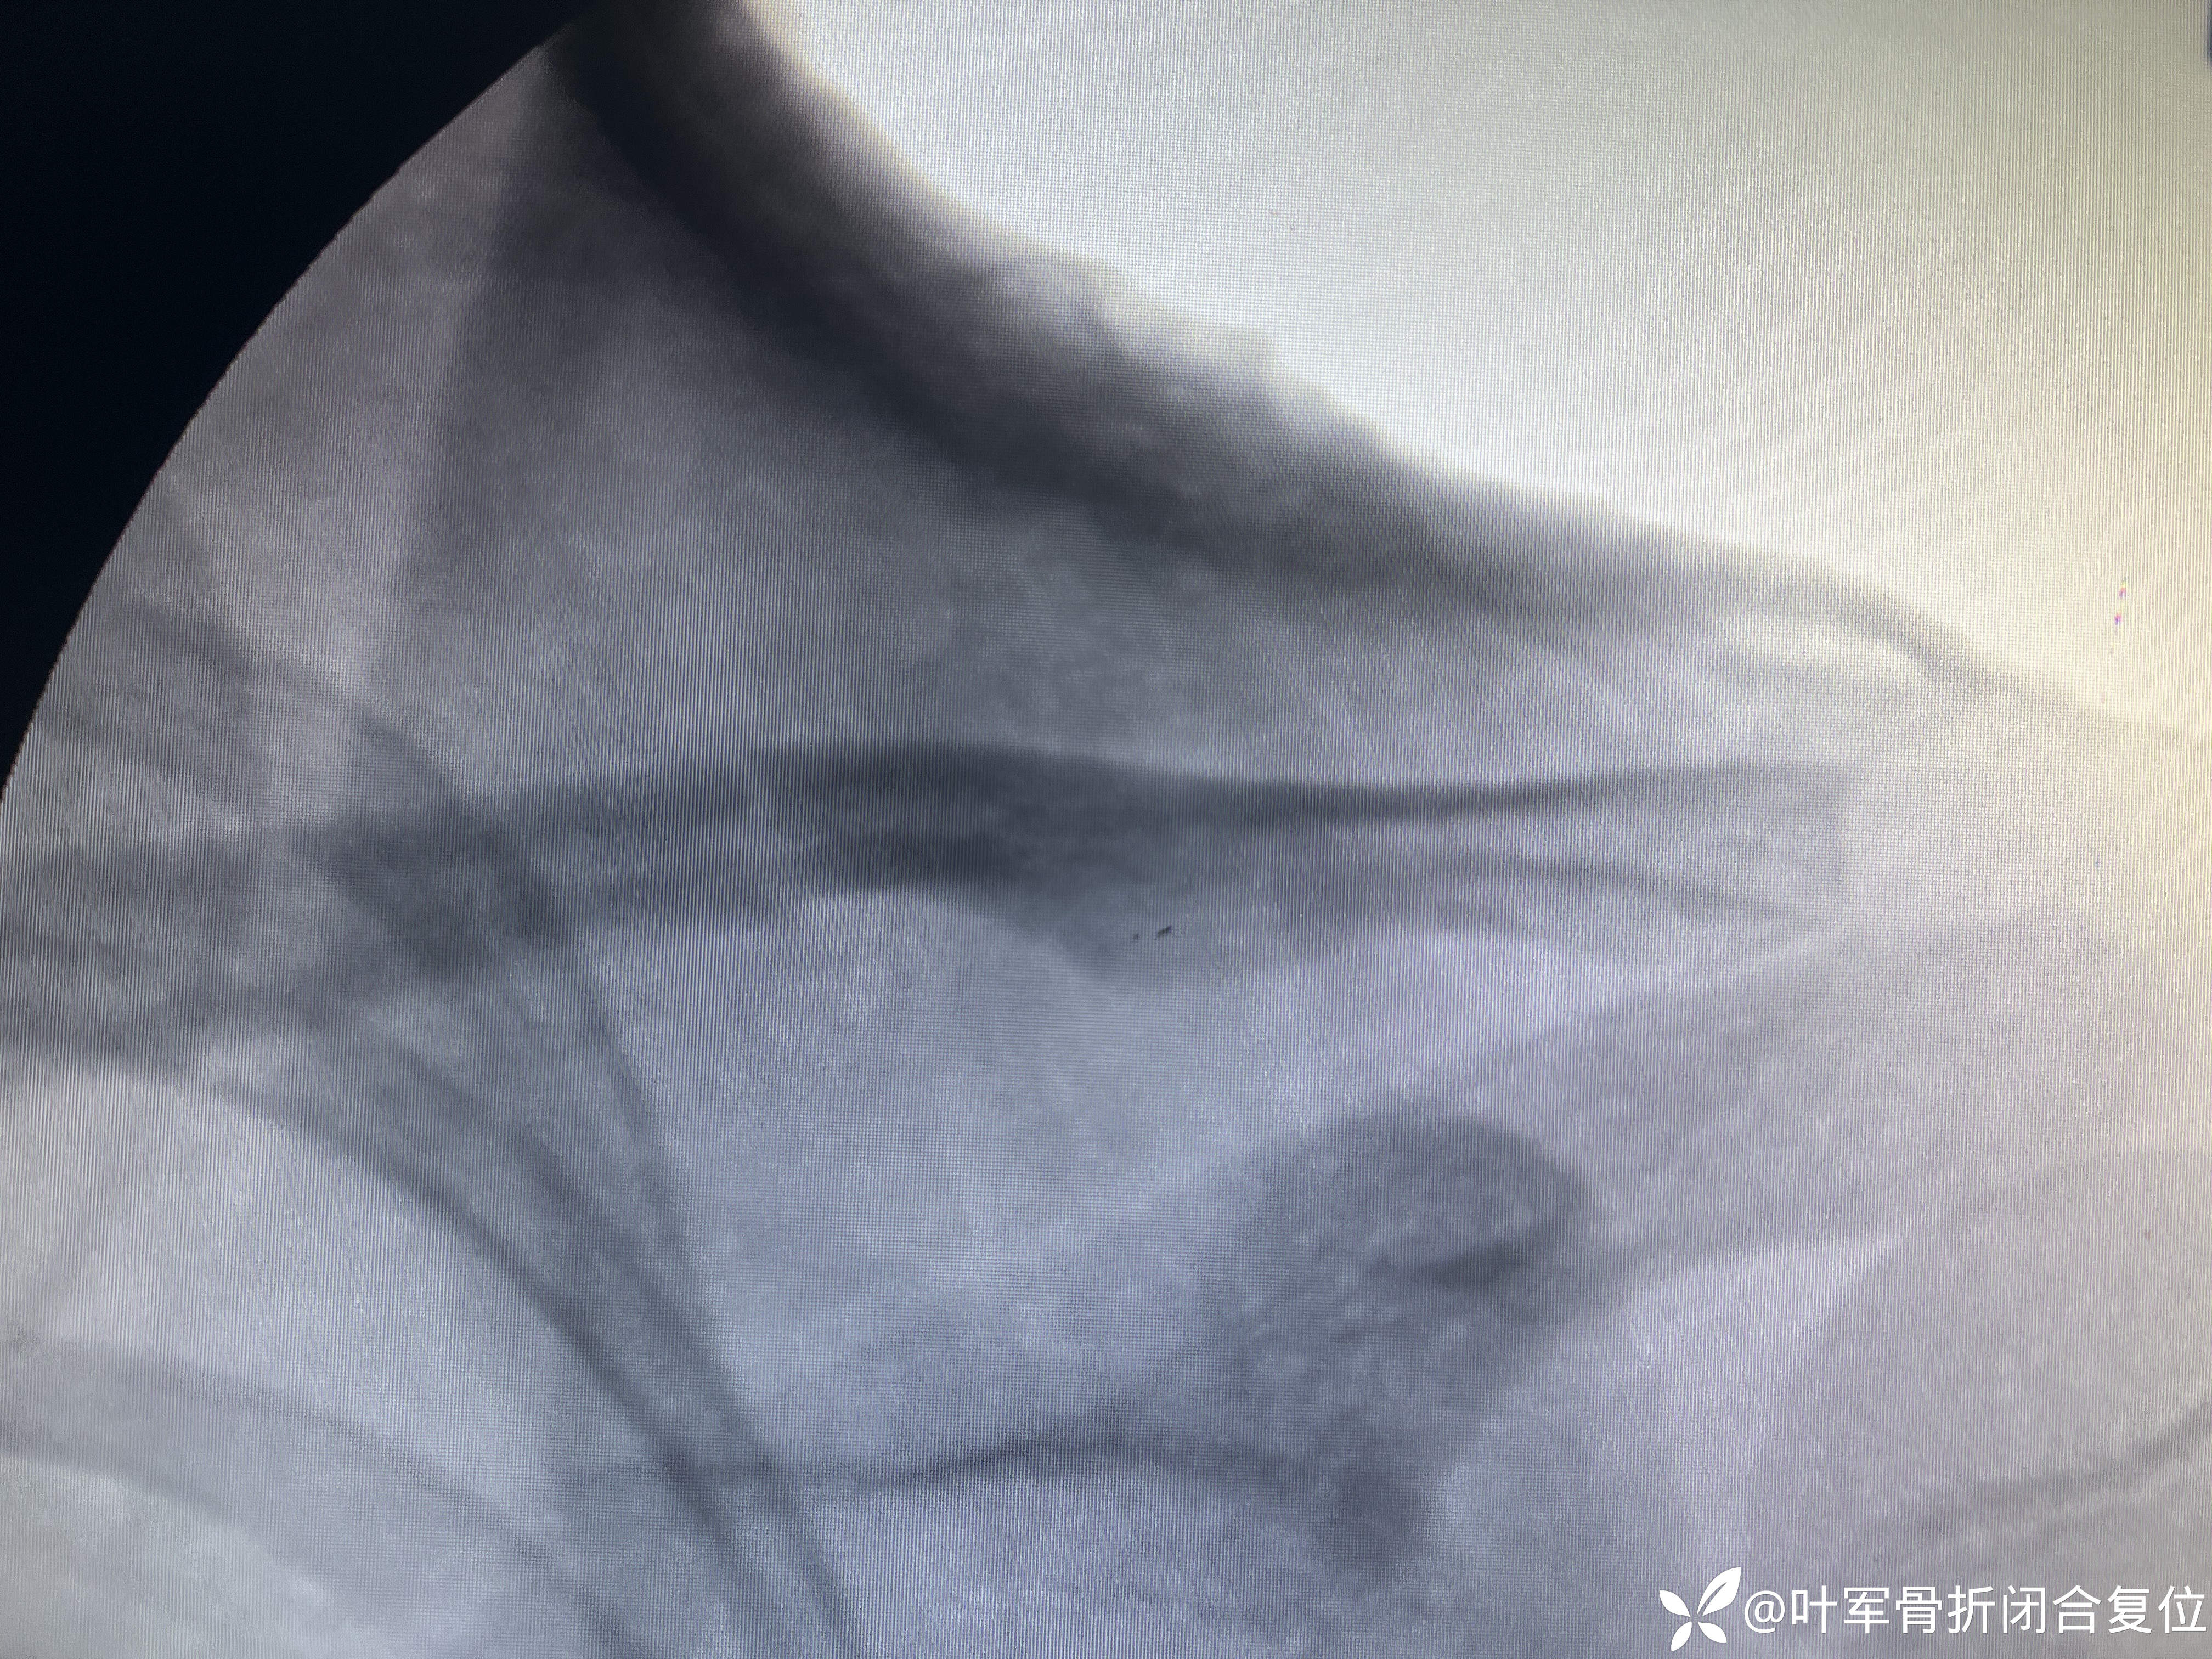

5. 评估:复位之后,医师审视骨折的排列,以确保其解剖位置恰当。

复位情况

6. 固定:得到满意的复位后,以石膏绷带固定,以保持骨折处的解剖复位,助其愈合。